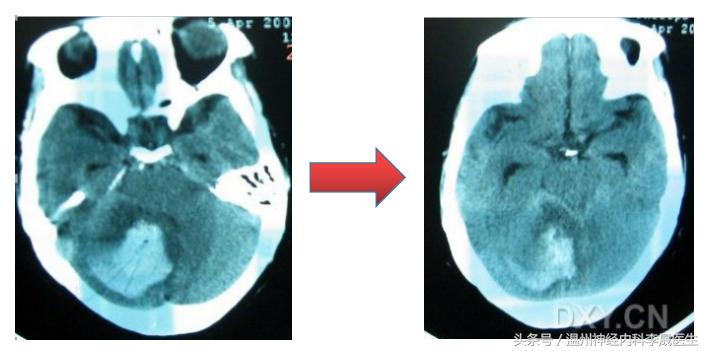

2、小脑出血,易形成脑疝

出血量≥10ml,或直径≥3cm,或合并脑积水,应尽快手术治疗。